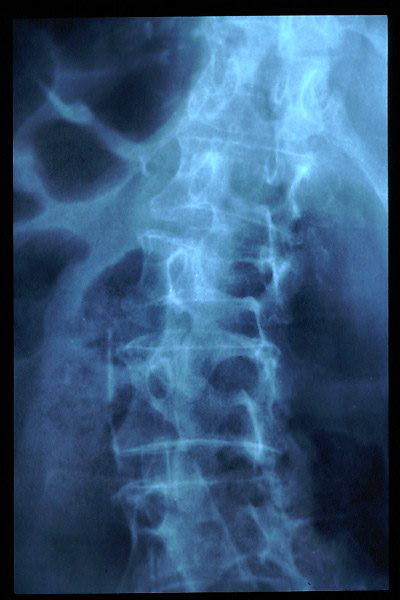

Osteoporosis. Cifosis.

Artrosis lumbar con pinzamiento.

Artrosis lumbar

Escoliosis, artrosis, aplastamiento...